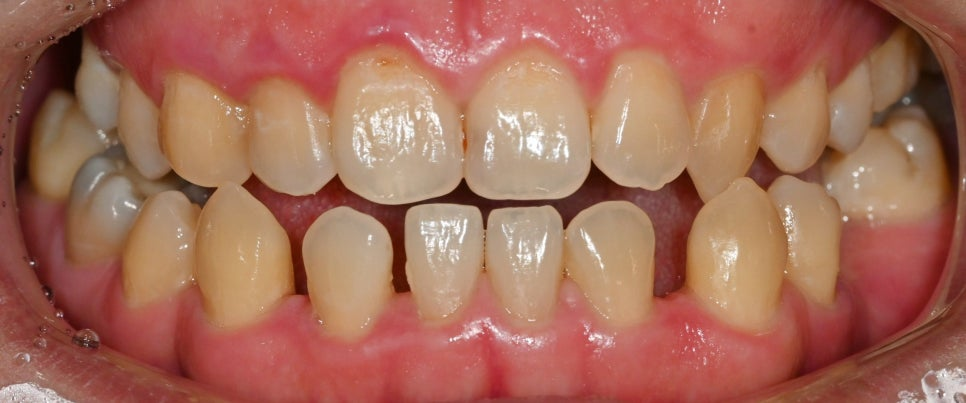

반대교합(Crossbite)은

정상적인 교합과 달리 아랫니가 윗니보다 앞으로

나와 있는 상태를 의미합니다.

이것들이 동시에 있을 경우

치아 배열이 전체적으로 불안정해지는 것을

확인할 수 있어요.

치아 사이 간격이 비정상적으로

넓어지면서 치간이개가 생기고,

맞물려야 될 이가 제대로

접촉하지 못하게 됩니다.